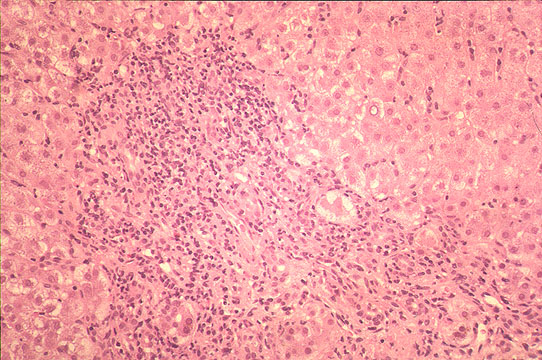

Fig 111 - Marked Inflammation of all portal fields. Notice three portal fields infiltrated by inflammatory cells with erosion of limiting plates. Score=4

Interface hepatitis

Fig 112 - Interface hepatitis: Marked mononuclear

infiltration of all portal tracts with erosion of limiting

plates and piecemeal necrosis. Score=4

Lobular inflammation

Fig 113 - Lobular inflammation: There is no confluent

necrosis but there is focal necrosis with Councilman bodies,

one with a pyknotic nucleus. Score=2

Fibrous changes

Fig 114 - Fibrous changes: Fibrous expansion of all portal

fields with occasional portal-portal Bridging. Score=3